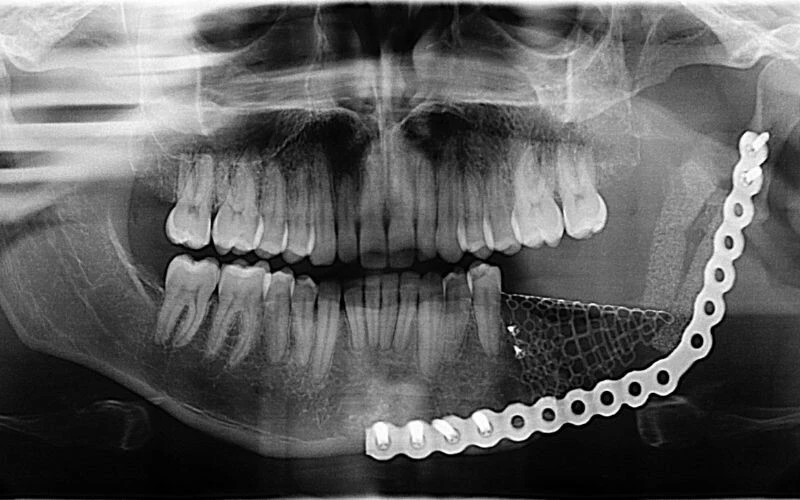

KTÜ'den yapılan açıklamaya göre, 2004'te çene kemiğindeki kemik tümörü nedeniyle Farabi Hastanesi'nde ameliyat edilen Karakaya, 19 yıl süren periyodik takiplerinde sağlıklı şekilde hayatına devam etti.

Anadolu Ajansı'ndan aktarılan bilgiye göre; Bu yıl mart ayında yüzünün sağ yarısında şişlik fark eden ve hastanenin Kulak Burun Boğaz Kliniği'ne (KBB) başvuran Karakaya'nın yapılan tetkiklerinde, tümörün bu kez yüzündeki elmacık kemiğini etkilediği belirlendi. Doç. Dr. Bengü Çobanoğlu tarafından değerlendirilen Karakaya, tümörün vücudunun başka yerine sıçramadığının belirlenmesinin ardından ameliyata alındı. Operasyonla elmacık kemiğiyle birlikte tümör de çıkarılan Karakaya, yara iyileşmesi tamamlandıktan sonra sağlığına kavuştu.

Operasyonu gerçekleştiren ekibi yöneten Doç. Dr. Bengü Çobanoğlu, hızlı hareket ederek ameliyatla tümörü çıkarttıklarını belirtti. Çobanoğlu, operasyon sonrası yara iyileşmesinin de başarılı şekilde tamamlandığını vurgulayarak, hastasının sağlığına kavuşmasından duyduğu memnuniyeti aktardı. Baş-boyun bölgesinde meydana gelen tümörlerin ciddi sağlık sorunlarına yol açabildiğine dikkati çeken Çobanoğlu, şunları kaydetti: